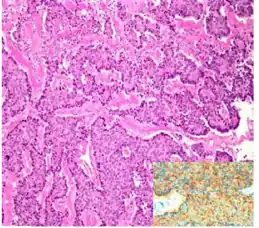

| Micrograph of a strumal carcinoid. H&E stain. | |

The strumal carcinoid is a type of monodermal teratoma with histomorphologic features of (1) the thyroid gland and (2) a neuroendocrine tumour (carcinoid).[1][2]